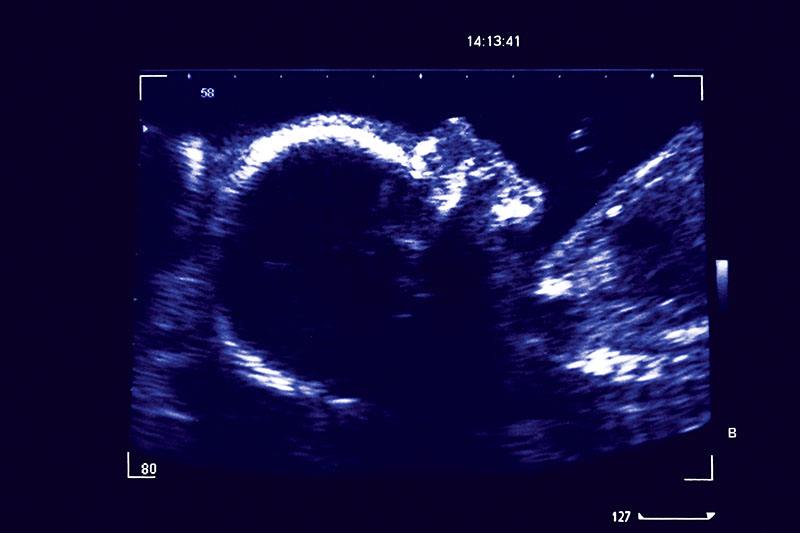

26 Weeks Pregnant Ultrasound | Www.imgkid.com - The Image Kid Has It!

imgkid.comultrasound semanas embarazo fetus fetal feto minggu hamil babymigo belly momtricks pregna

imgkid.comultrasound semanas embarazo fetus fetal feto minggu hamil babymigo belly momtricks pregna